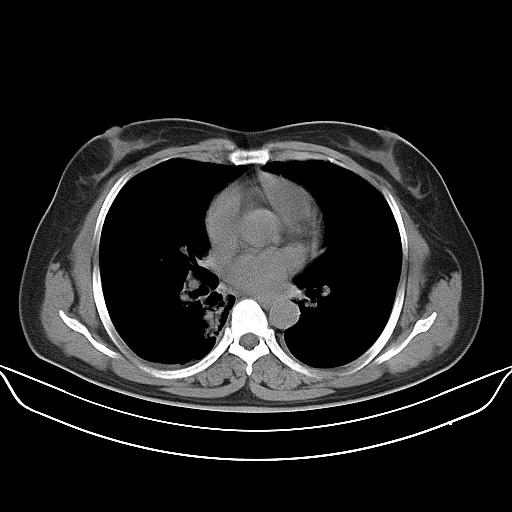

标题: CT22224:肺部肿块

f,48,主因咳嗽咳血来我院检查,无发热。

1)右肺下叶背段团块状软组织密度影;建议抗炎治疗后复查排除肿瘤性病变。2)右侧少量胸腔积液。

谈一谈个人的看法:机器性能应该不错,可惜扫描方法不太正确,即没有及时薄层扫描图像,也没有增强检查,这样的检查方法不正确的图片拿来研究只能是猜一猜:右肺下叶阻塞性改变,建议进一步检查删除肺癌。

支气管镜检查未见异性细胞,抗炎治疗20天,肿块明显缩小。